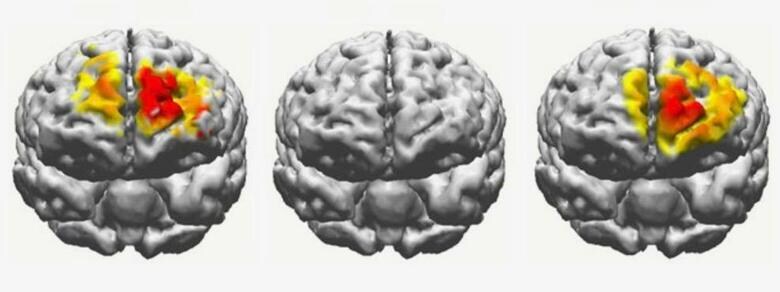

実験では、60〜76歳の高齢者42人と対照群の20〜29歳の若者42人に、よく似た2枚の画像を連続して見せて、異なる部分を指摘させるというテストを実施。電気刺激を与える前のテストでは、若者のほうが高齢者よりもはるかに正確だった。

その後、高齢者には各自の脳のリズムに調整した電気刺激を25分間与えてからテストを再度実施したところ、正解率は20代とほぼ同じ水準にまで向上した。また、記憶の改善は刺激を加えてから約50分間持続したという。